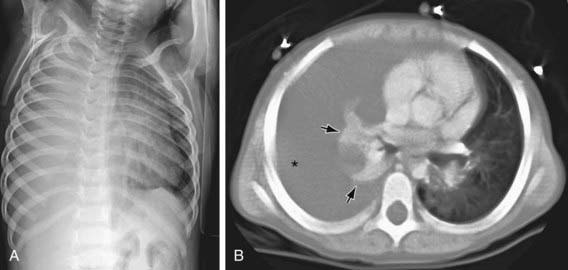

image

Figure 409-3 Large right chylous effusion opacifying much of the right thorax in a teenager with pulmonary lymphangiomatosis and hemangiomatosis. Note the associated interstitial lung disease.